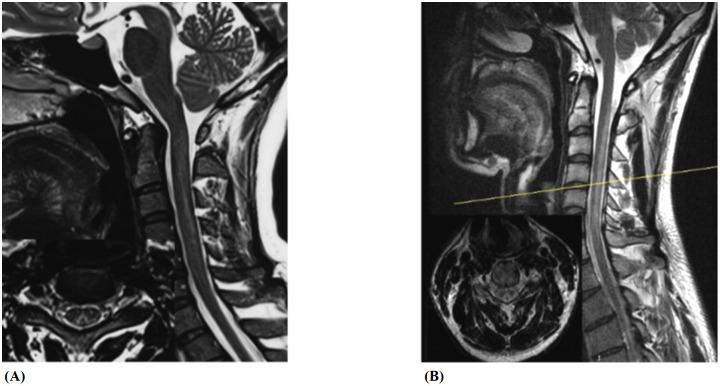

The aim of this study was to compare the clinical presentations, nerve conduction studies, neuroimaging findings of subacute combined degeneration (SCD) caused by NO abuse and primary vitamin B12 deficiency. The goal is to improve diagnostic accuracy, tailored therapeutic interventions, and ultimately enhancing patient outcomes in cases of SCD caused by NO abuse.

This study was a retrospective case-control study which enrolled 23 patients diagnosed with NO-induced subacute combined degeneration (NO-SCD) and 20 patients with vitamin B12 deficiency-induced subacute combined degeneration (Vit B12-SCD) between 2015 and 2023. Clinical manifestations, physical examinations, laboratory tests, nerve conduction studies, and spinal cord MRI imaging results were collected. Additionally, age-matched healthy control groups were also included for comparative electrophysiological analysis, consisting of 23 young individuals and 21 elderly individuals corresponding to the NO-SCD and Vit B12-SCD groups, respectively.

The study found that compared to Vit B12-SCD, NO-SCD patients exhibited more severe and extensive neurological damage. Both NO-SCD and Vit B12- SCD patients may present with numbness or abnormal sensations, limb weakness, difficulty walking and inability to walk, but these are more severe and widespread in NO-SCD patients. NO-SCD patients showed significant decreases in limb strength, with common walking difficulties and paralysis. Additionally, NO abuse patients more frequently exhibited psychiatric symptoms, especially memory loss, hallucinations and confusion. Both Vit B12-SCD and NO-SCD can cause peripheral nerve demyelination and axonal damage, but it is more severe in the NO-SCD group, with more damage in the lower limbs than in the upper limbs. The extensive nature of axonal damage also indicated a poor prognosis. The degree of spinal cord damage in the NO-SCD group was more severe and affected longer segments. These results suggest that in addition to affecting vitamin B12, NO also causes neurological damage through other mechanisms.

研究发现,与Vit B12-SCD相比,NO-SCD患者表现出更严重、更广泛的神经损伤。NO-SCD和Vit B12-SCD患者均可能出现麻木或异常感觉、肢体无力、行走困难及无法行走,但这些症状在NO-SCD患者中更严重、更广泛。NO-SCD患者肢体力量显著下降,常见行走困难及瘫痪。此外,NO滥用患者更常出现精神症状,尤其是记忆力减退、幻觉和意识模糊。Vit B12-SCD和NO-SCD均可导致周围神经脱髓鞘和轴突损伤,但在NO-SCD组更严重,下肢损伤比上肢更严重。轴突损伤的广泛性也表明预后不良。NO-SCD组脊髓损伤程度更严重,累及节段更长。这些结果表明,NO除了影响维生素B12外,还通过其他机制导致神经损伤。